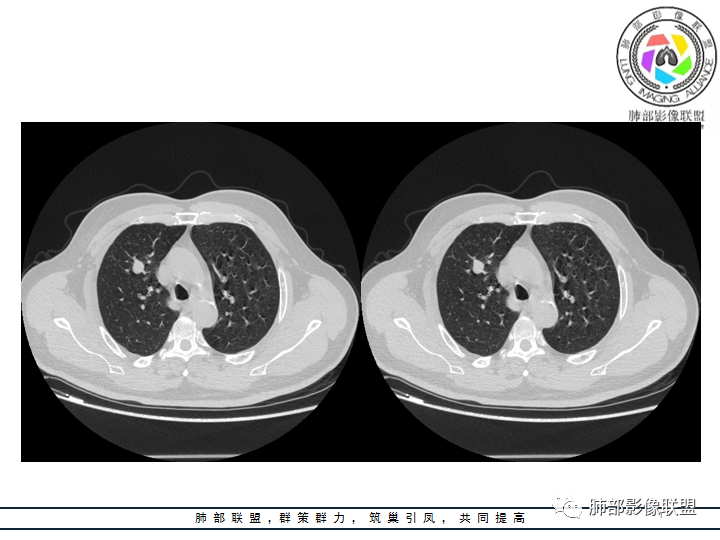

影像资料

老年男性患者,长期吸烟史,没有呼吸系统临床表现。胸部CT示右肺上叶实性密度结节影,密度均匀,未见空洞及钙化,边缘较光整,未见分叶及毛刺。血管影旁现侧出,支气管进入并截断,不均匀强化。